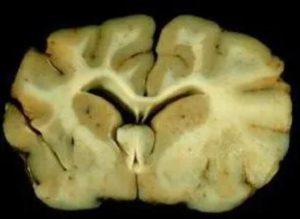

FDA接受OTL-200在异染性脑白质营养不良中的生物制品许可证申请并获得优先审查

近日,全球基因疗法领导者Orchard Therapeutics(Nasdaq:ORTX)宣布,美国食品和药物管理局(FDA)已接受其OTL-200在异染性脑白质营养不良(MLD)治疗方面的生物制品许可申请(BLA),并予以优先审查。 FDA已经设定了截止日期,PDUFA目标日期为2024年3月18日。 “对于长期以来一直遭受这种毁灭性而残酷疾病影响的美国患者和家庭来说,今天是向前迈出的又一个重要步伐。他们太久以来一直承受着难以想象的诊断之旅的重负,被告知除了支持性治疗之外没有其他治疗方法,然后不得不看着自己的孩子消逝,”Orchard Therapeutics联合创始人兼首席执行官Bobby... 查看详情